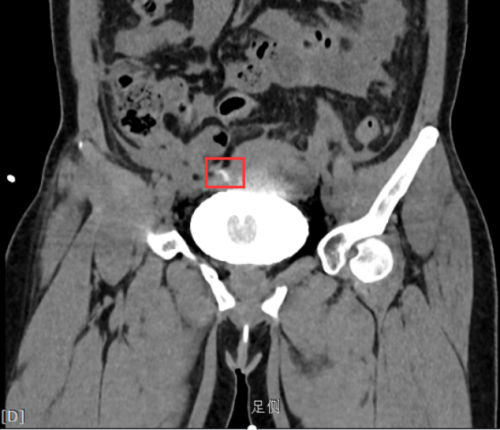

危急时刻,由泌尿外科、普外科和放射科组成的MDT团队迅速启动应急诊疗方案。放射科团队创新性地采用逆行性CT膀胱造影技术:通过尿道导管精准注入恒温造影剂,结合256层螺旋CT动态扫描,成功捕捉到膀胱顶壁一处细微的造影剂外渗征象。三维重建图像清晰显示病灶位于膀胱穹顶区,呈现特征性的“星芒状”渗漏模式。

膀胱穹顶区可见“星芒状”(红框内)渗漏

基于放射科提供的精准影像定位,当晚泌尿外科与普外科团队联合为李女士实施急诊手术。术中所见与影像诊断完全吻合:膀胱顶壁存在直径约0.5cm的陈旧性憩室破裂口,周围被大网膜包裹形成假性闭合。手术团队顺利完成膀胱修补和腹腔脓液清除,术后病理证实为慢性炎症导致的膀胱壁薄弱破裂。